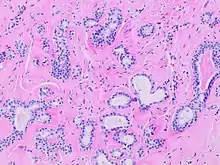

![]() Human submandibular gland. At the right is a group of mucous acini, at the left a group of serous acini. | |